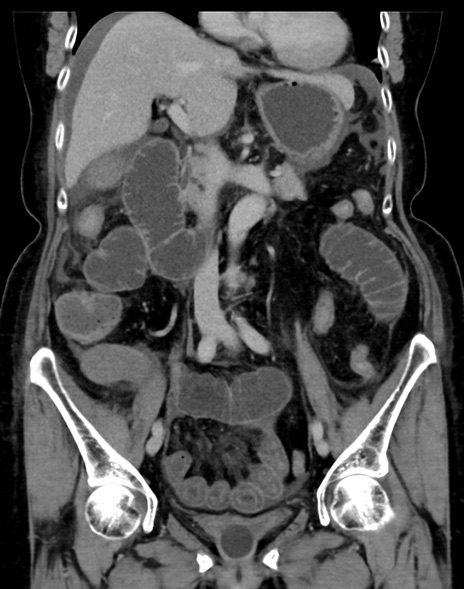

症例13 CT(冠状断像)1日半後